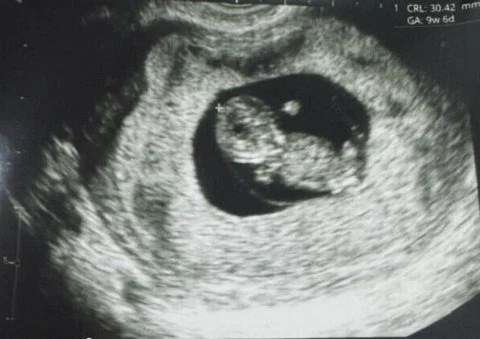

Уникальный случай в Перу: ребенок, зачатый благодаря созреванию яйцеклетки вне организма

Малыша уже называют уникальным, о его рождении объявила американская биотехнологическая компания Gameto, которая специализируется на совершенствовании методов поддержания женского здоровья. Ребёнок родился с использованием новой технологии Fertilo, которая, по сути, является типом экстракорпорального оплодотворения (ЭКО). Она позволяет проводить процесс созревания яйцеклетки вне тела женщины с помощью поддерживающих клеток яичника, полученных в лаборатории из стволовых клеток.